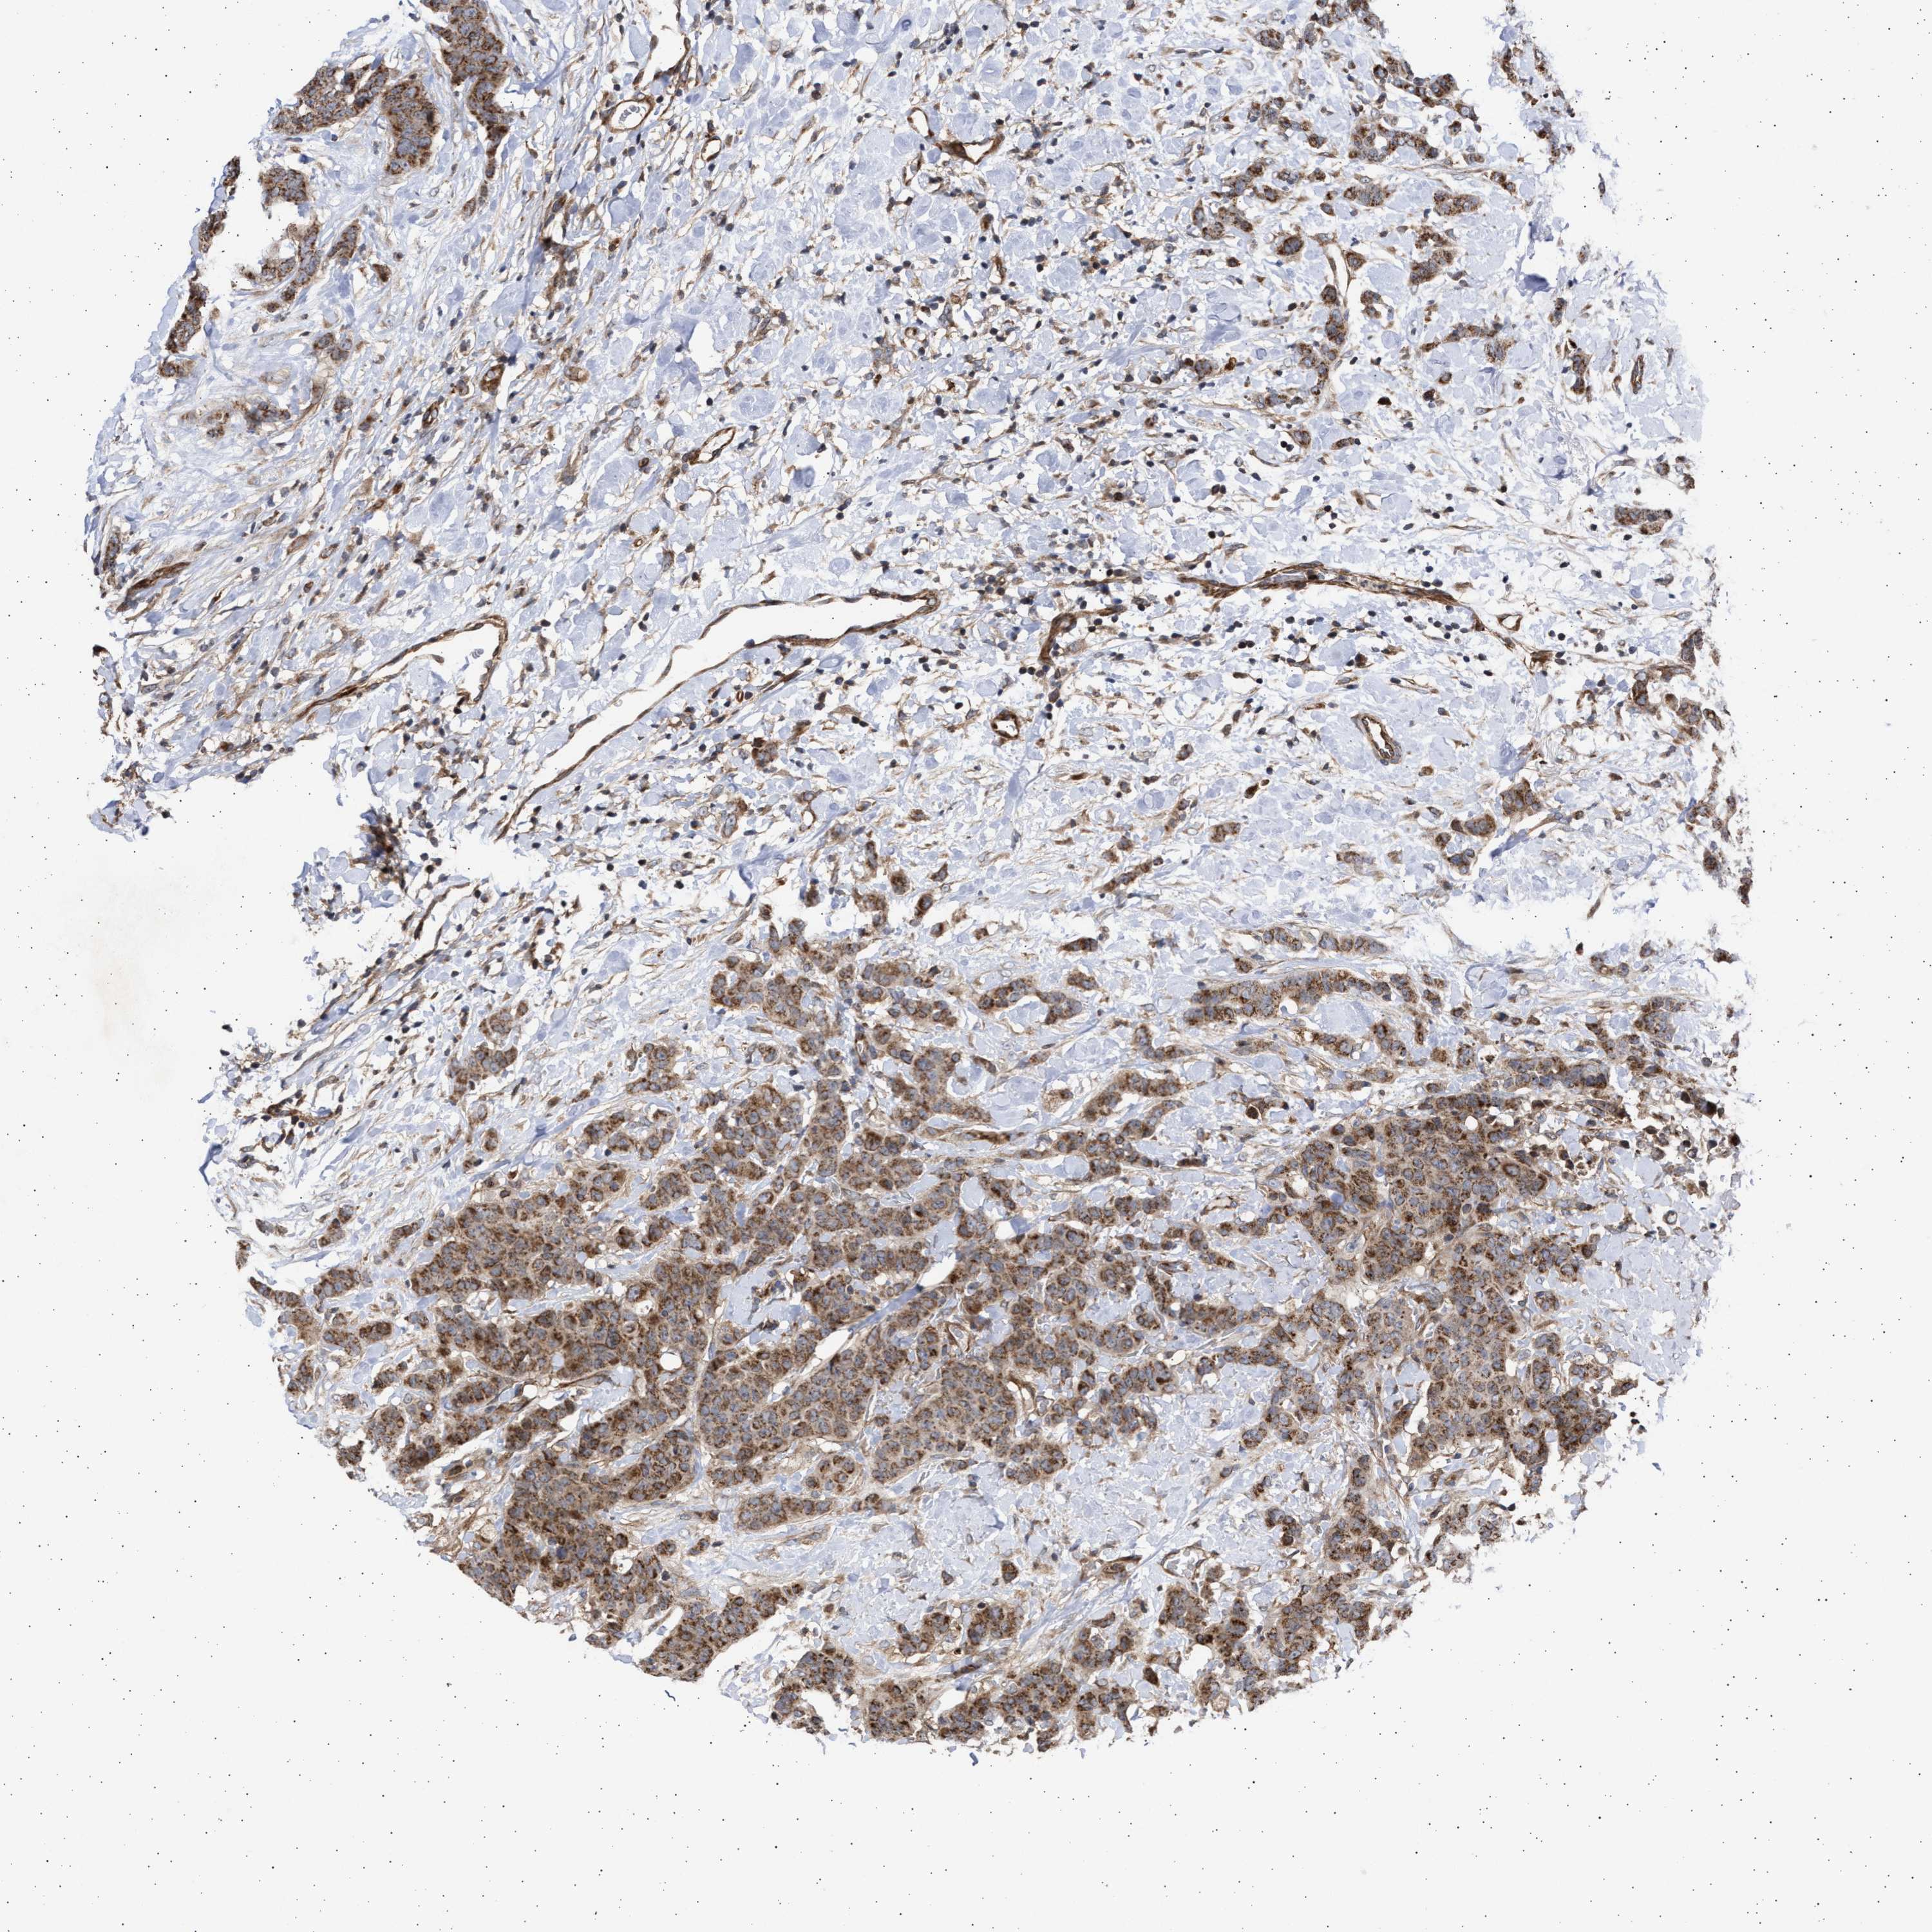

CANCER BREAST CANCER Show tissue menu

BRCA TCGA BRCA VALIDATION PROTEIN EXPRESSION

ANTIBODIES

AND

VALIDATION